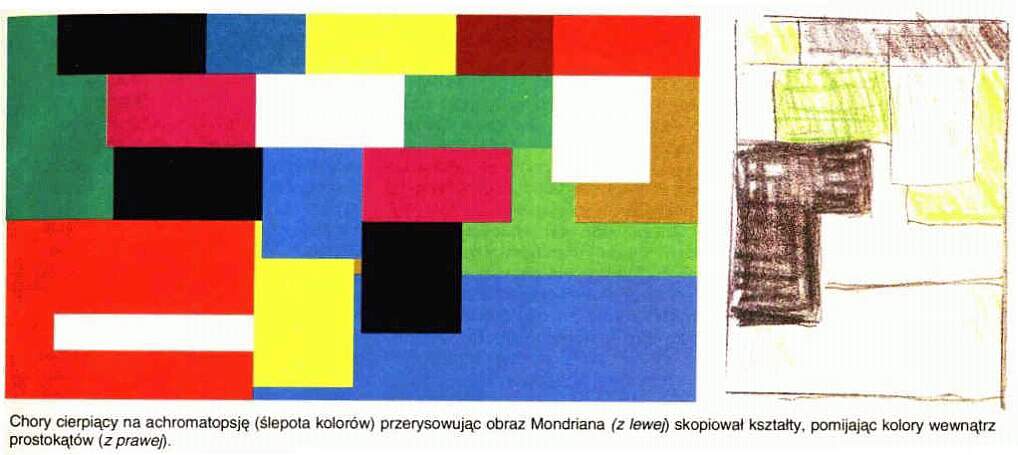

Uszkodzenia obszaru V4 prowadzą do

mózgowej achromatopsji, ślepoty barw, czyli zaniku zdolności do widzenia kolorów.